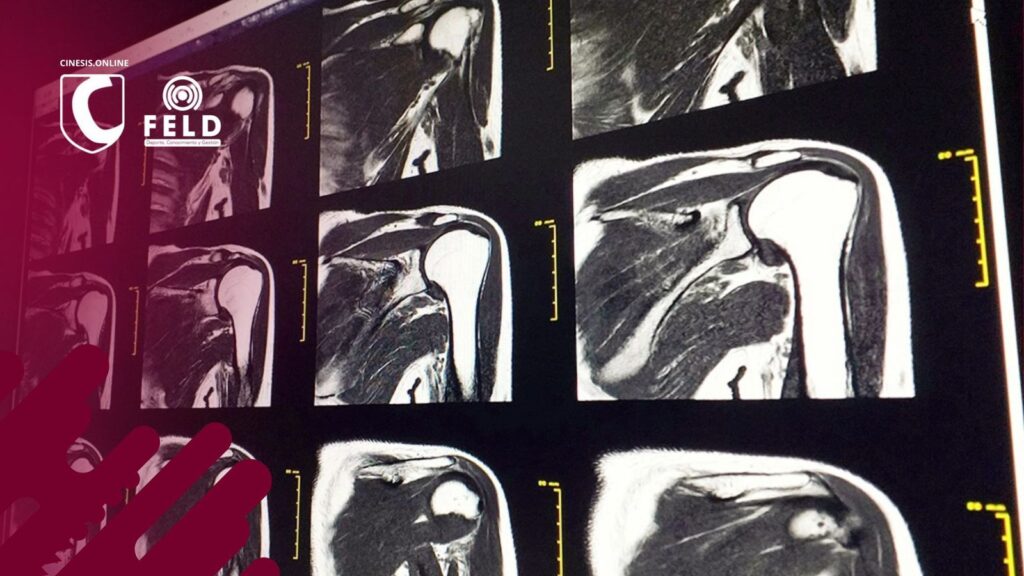

¿Qué sucede con los estudios por imágenes en pacientes con dolor de hombro?

En la práctica diaria, el dolor de hombro es uno de los motivos de consulta más frecuentes (entre el segundo y el cuarto en Argentina, Policastro y cols. 2020). Y siempre aparece la misma pregunta: ¿los estudios de imagen son realmente necesarios? Por un lado, sabemos que existe la necesidad de respaldo médico‐legal y, sobre […]